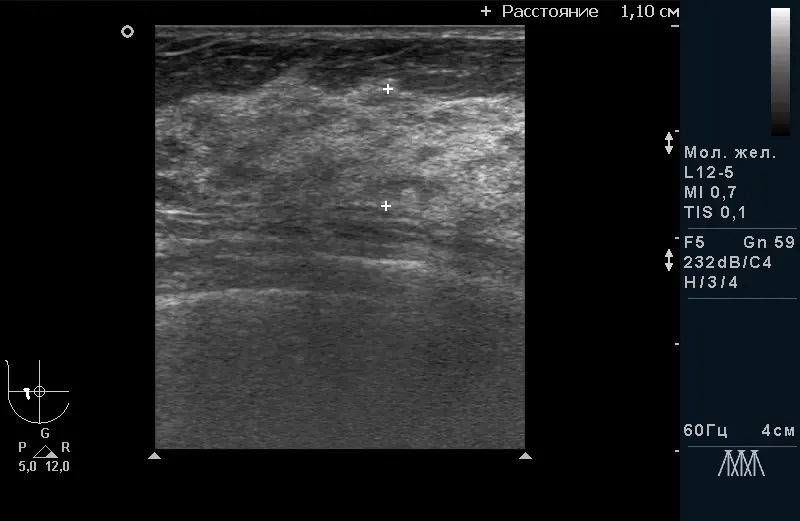

Рис.2. Дифузна форма мастопатії без гіперплазії і фіброзу. |